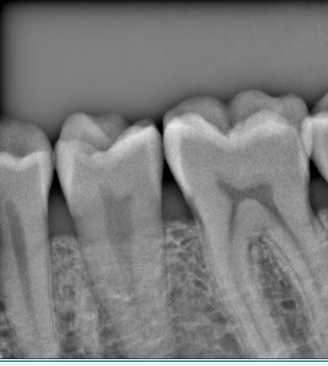

Digital X Ray

With our latest KODAK Intraoral Radiography technology we are proud to offer our valued patients with high-quality Digital X-rays. The advantages of Digital X-rays for our dental patients include the following:

• Reduced Exposure to Radiation. The amount of radiation used in digital x-rays is reduced by up to 80% over conventional film x-rays.

• Immediate and Convenient. The pictures are available for viewing within seconds.

• Better Quality. Diagnosis is more accurate and retakes are less frequent.

Logicon Cavity Detector

At Radiant Smiles, we emphasize on Preventive Dentistry in order to provide excellent Oral Health. We proudly utilize LOGICON Cavity Detector Software with KODAK intraoral digital X-ray Radiography systems to help us identify non-visible cavities early on.

• LOGICON is dental software made by Carestream Dental that is clinically proven to help dentists find 20% more interproximal cavities than possible with traditional methods.

• LOGICON Caries Detector Software™ is a unique powerful computer-aided diagnostic (CAD) tool that assists a dentist in the difficult task of diagnosing x-rays for cavities in between the teeth.

• LOGICON Software takes image features and compares them with a database of known cavity problems. In doing so, the software automatically highlights possible problem areas in a patient's digital dental x-rays, signaling to the dentist to take a closer look at the tooth involved. This software color-codes the cavities for easier viewing and it also indicates the penetration depth of cavities.